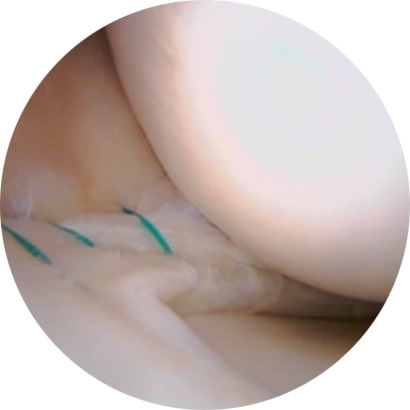

불안정한 반월상연골 부위를 내시경으로 확인하여 파열된 연골판을 꿰맴

반월상 연골판 파열 정도에 따라서 절제술, 봉합술로 나눠 수술을 결정합니다.